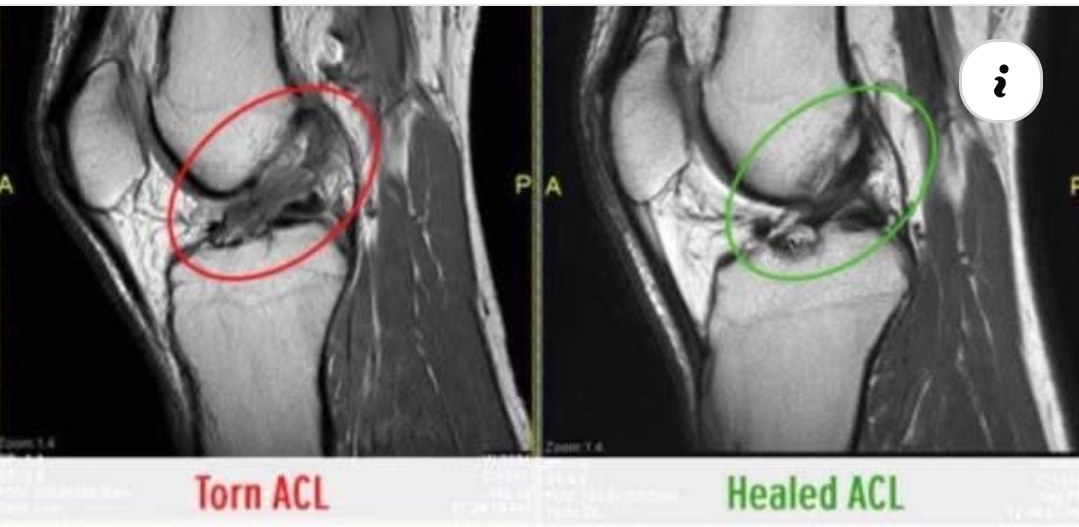

Are you Looking for Physiotherapy Treatment in Tambaram, Sunshine Super Speciality Physiotherapy Clinic, We Provide Electrotherapy, Exercise and Manual Therapy, Orthopedic, Neuro, Cardio, Pediatric, Sports and Geriatric Rehabilitation, Post Operative Physiotherapy Treatment, Fracture Rehabilitation, pain free movement.